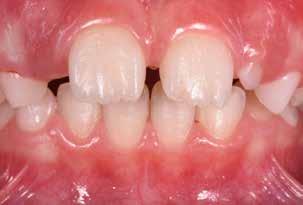

Presentazione del caso > F.V, bambino di cinque anni, presenta una malocclusione di II Classe scheletrica, III Classe dentale molare e canina destra e sinistra, morso inverso anteriore. Le arcate dentali mostrano usura degli elementi dentari anteriori a causa dell’occlusione patologica. Le linee mediane, superiore ed inferiore, sono centrate; il frenulo labiale superiore patologico per un’eccessiva estensione inter-incisale.

Dall’esame clinico si evince la III Classe dentale, l’inversione anteriore e l’over-jet negativo.

Una volta ottenuta la correzione del rapporto molare ed incisale, l’apparecchio elastodontico verrà portato dal paziente solo durante la notte per stabilizzare il risultato ottenuto e guidare l’eruzione degli elementi dentari per un totale di quattordici mesi di terapia. ad inizio trattamento :

Considerazioni > L’analisi cefalometrica ad inizio trattamento dimostra la II Classe scheletrica con protrusione del mascellare superiore e prognazia mandibolare; tendenza alla crescita verticale. L’esame clinico evidenzia una protrusione mandibolare funzionale.